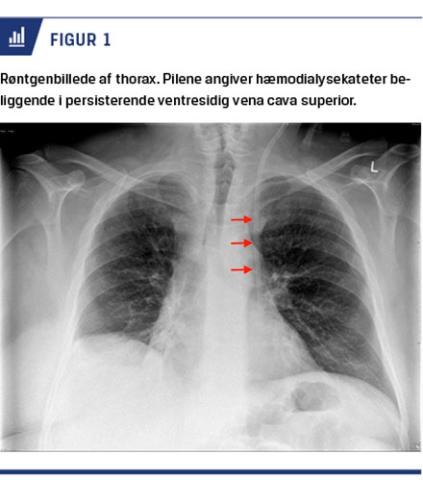

En 55-årig patient, der havde nefropati og var i dialyse, blev indlagt med sepsis, sandsynligvis udgået fra en dysfungerende atrioventrikulær (AV)-fistel i en overekstremitet. Pga. anuri og hyperkaliæmi var der akut behov for hæmodialyse og derfor HD-kateteranlæggelse. Suboptimale forhold på højre side af halsen medførte ultralydvejledt anlæggelse i venstre VJI. Anlæggelsen foregik ukompliceret, hvorefter dialysen kunne påbegyndes efter kontrol af kateterbeliggenhed. På en røntgenoptagelse af thorax sås kateteret placeret i venstre side af thorax med spidsen over venstre side af hjertet (Figur 1). Dialysen blev påbegyndt alligevel,

da der var frit ind- og udløb af veneblod, bestemt ved blodgasanalyse, og den blev gennemført med god kvalitet. Man havde på baggrund af en sideoptagelse med røntgen mistanke om, at kateteret var placeret i venstre vena thoracica interna, og det blev, under gennemlysning, forsøgt omlagt mod (højresidig) VCS, dog uden held. Trods dialyse af god kvalitet blev det pga. usikkerhed om placeringen besluttet at genanlægge HD-kateteret via lysken. En tidligere hjerte-CT viste dog, at patienten havde dobbeltanlæg af VCS, og HD-kateter-